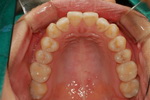

| ÃæÄ¡Ä¡·á¿Í Ä¡¾Æ¼ºÇü |

| ÃæÄ¡Ä¡·á Àη¹ÀÌ¿Í Å©... |

| ÃæÄ¡ ±ÝÀη¹ÀÌ¿Í ·¹Áø |

| ÃæÄ¡ Ä¡·á |

| ÃæÄ¡Ä¡·á |